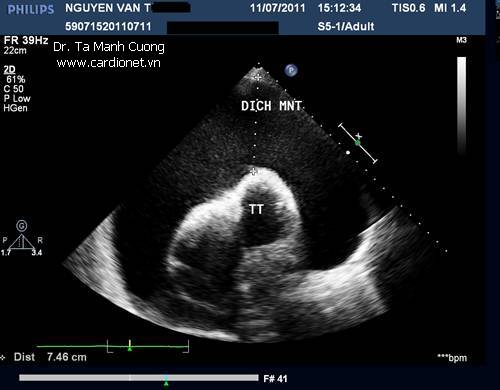

Tràn dịch màng ngoài tim lượng dịch rất nhiều

Tràn dịch màng ngoài tim lượng dịch rất nhiều gây ép xẹp toàn bộ thất phải trên siêu âm

Một số hình ảnh tràn dịch màng ngoài tim lượng dịch rất nhiều làm cho tim như bơi trong nước: